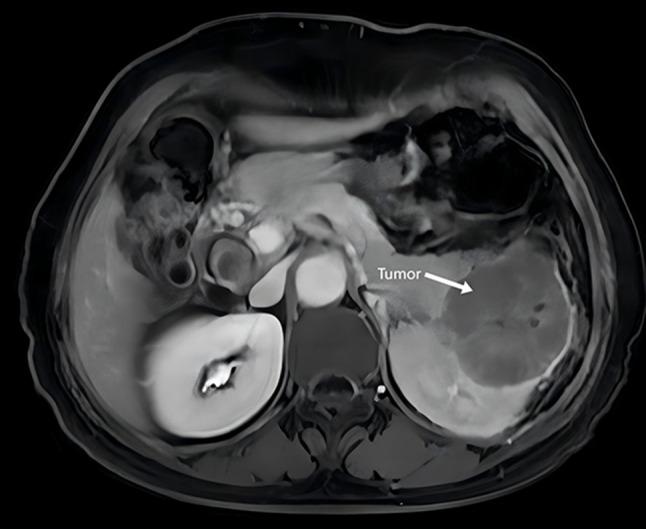

We present a rare case of unclassified renal cell carcinoma (RCC) in a 66-year-old woman, exhibiting multi-organ invasion. The patient was asymptomatic until a health exam revealed a left renal mass. CT scans showed an irregular, 6.8 × 8.9 cm mass involving the renal sinus, with possible pancreatic infiltration and retroperitoneal lymph node metastasis. Intraoperative findings necessitated multi-organ resection, including the left kidney, spleen, and portions of the pancreas. Histopathology confirmed unclassified RCC, positive for CA-9, CD10, Vim, and negative for P504S, CD99, Desmin. Post-surgery, the patient received cabozantinib and nivolumab, and remains progression-free at 22 months of follow-up. This case analyzed the diagnosis and treatment of aggressive unclassified RCC, and showed good efficacy after extensive surgical resection and combined treatment with cabozantinib and nivolumab, which may help further study of unclassified RCC.

我们报告了一例66岁女性的罕见未分类肾细胞癌(RCC)病例,该病例呈现多器官浸润。患者在健康检查发现左肾肿物之前没有症状。CT扫描显示一个不规则的6.8×8.9厘米肿物,累及肾窦,可能有胰腺浸润和腹膜后淋巴结转移。术中发现需要进行多器官切除,包括左肾、脾脏和部分胰腺。组织病理学证实为未分类RCC,CA-9、CD10、波形蛋白呈阳性,P504S、CD99、结蛋白呈阴性。术后,患者接受了卡博替尼和纳武单抗治疗,在22个月的随访中仍无疾病进展。本病例分析了侵袭性未分类RCC的诊断和治疗,并显示在广泛手术切除以及卡博替尼和纳武单抗联合治疗后有良好疗效,这可能有助于对未分类RCC的进一步研究。